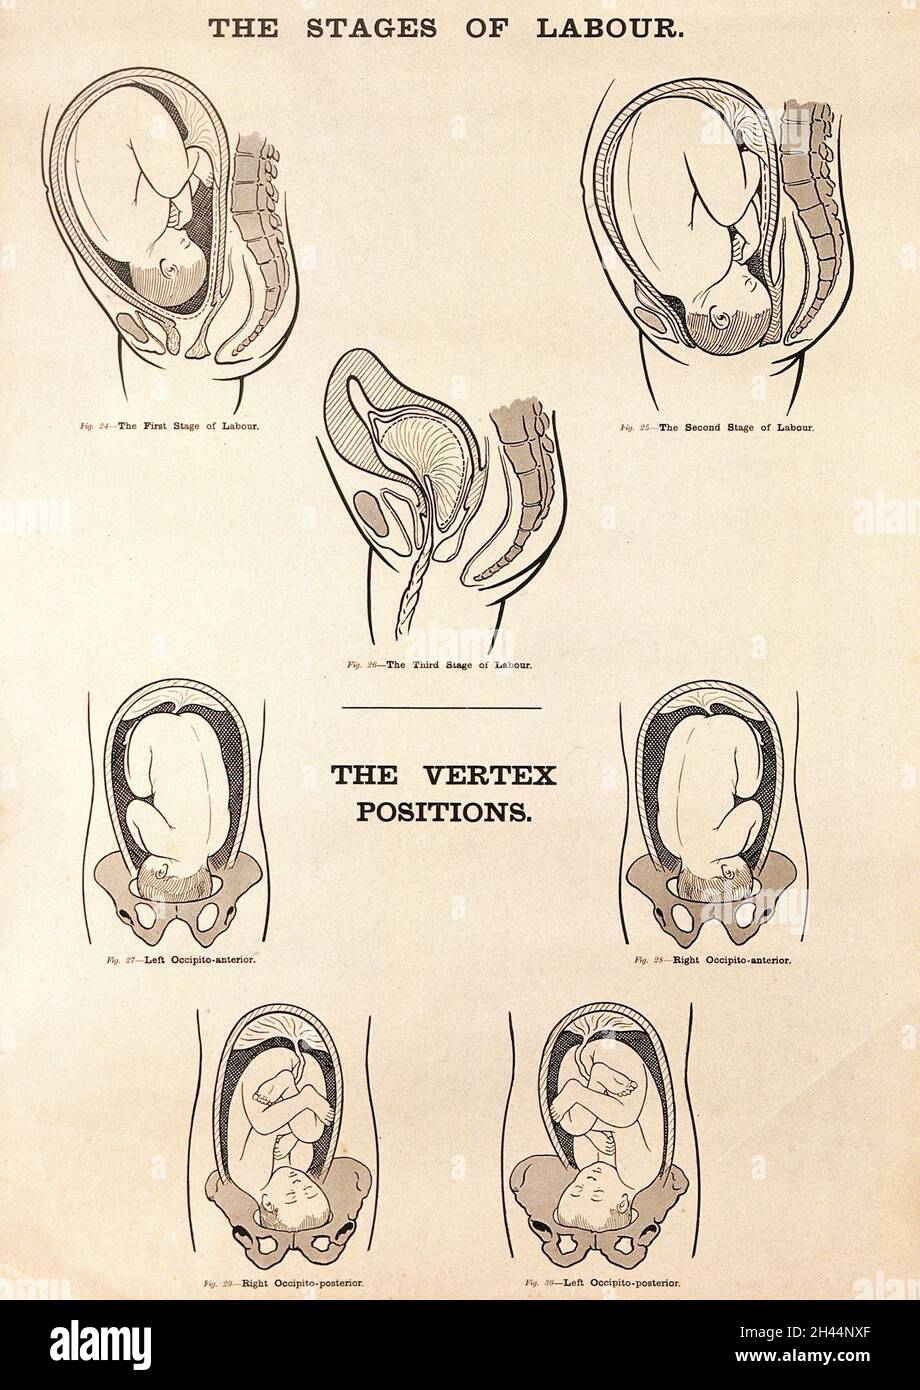

Eight diagrams illustrating babies in the womb in different positions about to enter the world. Etching by Barlow. Stock Photohttps://www.alamy.com/image-license-details/?v=1https://www.alamy.com/eight-diagrams-illustrating-babies-in-the-womb-in-different-positions-about-to-enter-the-world-etching-by-barlow-image449997775.html

Eight diagrams illustrating babies in the womb in different positions about to enter the world. Etching by Barlow. Stock Photohttps://www.alamy.com/image-license-details/?v=1https://www.alamy.com/eight-diagrams-illustrating-babies-in-the-womb-in-different-positions-about-to-enter-the-world-etching-by-barlow-image449997775.htmlRM2H434N3–Eight diagrams illustrating babies in the womb in different positions about to enter the world. Etching by Barlow.